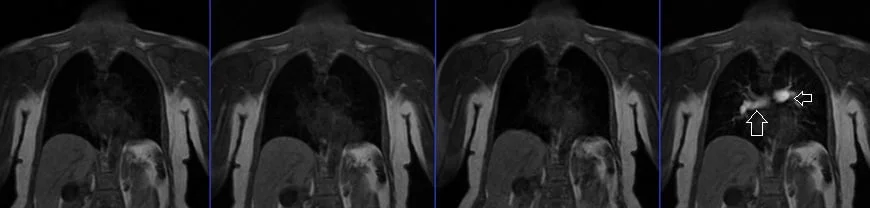

MRA subclavian arteries arm down

MRA subclavian arteries arm up